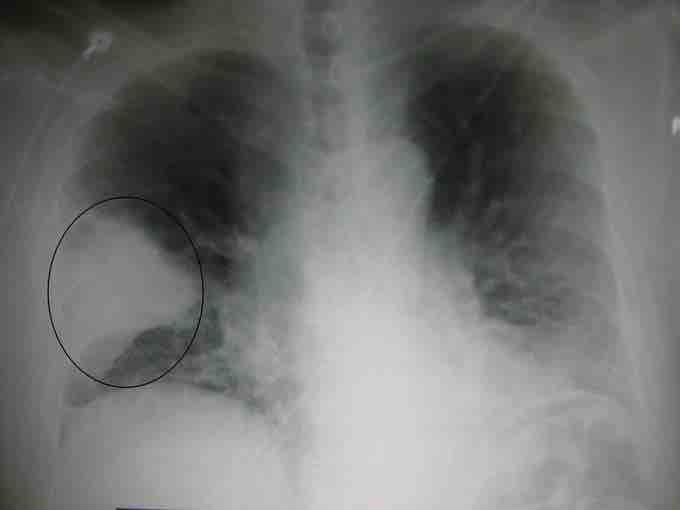

Bacterial pneumonia

A chest X-ray showing a very prominent wedge-shaped bacterial pneumonia in the right lung.

Bacteria are the most common cause of community-acquired pneumonia (CAP), with Streptococcus pneumoniae isolated in nearly 50% of cases . Other commonly isolated bacteria include: Haemophilus influenzae in 20%, Chlamydophila pneumoniae in 13%, and Mycoplasma pneumoniae in 3% of cases; Staphylococcus aureus; Moraxella catarrhalis; Legionella pneumophila and Gram-negative bacilli. A number of drug-resistant versions of the above infections are becoming more common, including drug-resistant Streptococcus pneumoniae (DRSP) and methicillin-resistant Staphylococcus aureus (MRSA). The spreading of organisms is facilitated when risk factors are present. Alcoholism is associated with Streptococcus pneumoniae, anaerobic organisms and Mycobacterium tuberculosis; smoking facilitates the effects of Streptococcus pneumoniae, Haemophilus influenzae, Moraxella catarrhalis, and Legionella pneumophila. Exposure to birds is associated with Chlamydia psittaci; farm animals with Coxiella burnetti; aspiration of stomach contents with anaerobic organisms; and cystic fibrosis with Pseudomonas aeruginosa and Staphylococcus aureus. Streptococcus pneumoniae is more common in the winter, and should be suspected in persons who aspirate a large amount anaerobic organisms.